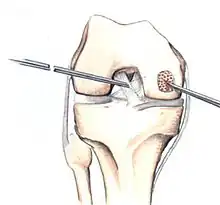

The articular cartilage along the border of the osteochondritis dissecans lesion

Arthroscopic image of OATS surgery on the medial femoral condyle of the knee

If non-surgical measures are unsuccessful, drilling may be considered to stimulate healing of the subchondral bone. Arthroscopic drilling may be performed by using an antegrade (from the front) approach from the joint space through the articular cartilage, or by using a retrograde (from behind) approach through the bone outside of the joint to avoid penetration of the articular cartilage. This has proven successful with positive results at one-year follow-up with antegrade drilling in nine out of eleven teenagers with the juvenile form of OCD,[53] and in 18 of 20 skeletally immature people (follow-up of five years) who had failed prior conservative programs.[54]